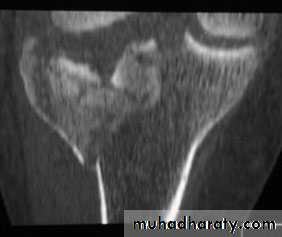

TIBIAL PLATEAU FRACTURES

Schatzker classification of Tibial Plataue Fracture

Type 1 – a vertical split of the lateral condyle.Type 2 – a vertical split of the lateral condyle combined with depression of an adjacent loadbearing part of the condyle.

Type 3 – depression of the articular surface with an intact condylar rim.

Type 4 – fracture of the medial tibial condyle.

Type 5 – fracture of both condyles.

Type 6 – combined condylar and subcondylar fractures.

Imaging

Anteroposterior, lateral and oblique x-rays will usually show the fracture, but the amount of comminution or plateau depression may not be appreciated without computer tomography (CT).Treatment